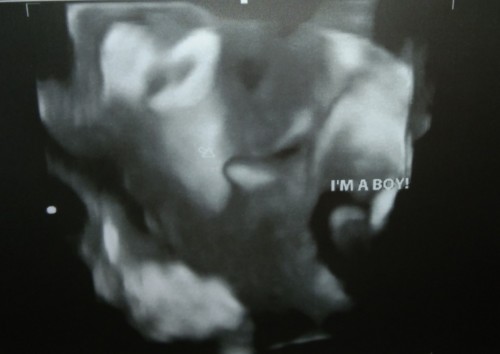

Mga mi, ask ko lang need ba talaga gawin Yung 75g ogtt, Kasi katapos ko lang mag FBS , mag kaiba pa ba yon mga mi,? Kasi naguluhan ako ,dame ata test sa sugar , pero sa mga friend ko, sa lying in sila nag papa check Wala daw sila na experience na Ganyan? Bat Ganon Po sa iba Wala. #1stimemom #advicepls #firstbaby